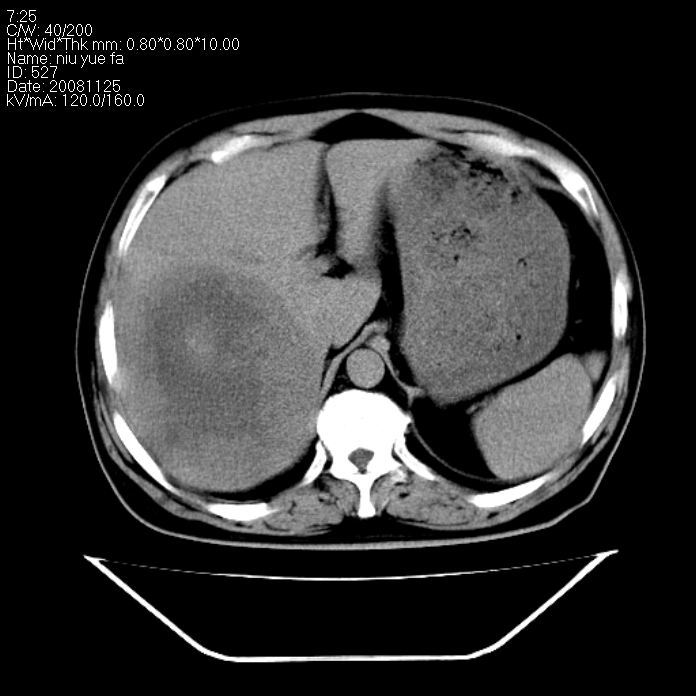

巨块型肝癌,坏死,出血;胆囊结石

1)考虑肝右叶巨块型肝癌并坏死、出血;建议行ct增强扫描检查进一步明确诊断。2)胆囊结石,胆囊炎。

考虑肝右叶巨块型肝癌并坏死、出血;建议行ct增强扫描。胆囊结石。

支持: 1)考虑肝右叶巨块型肝癌并坏死、出血;建议行ct增强扫描检查进一步明确诊断。2)胆囊结石,胆囊炎。

肝右叶巨块型肝癌并坏死、出血;胆囊结石,胆囊炎。